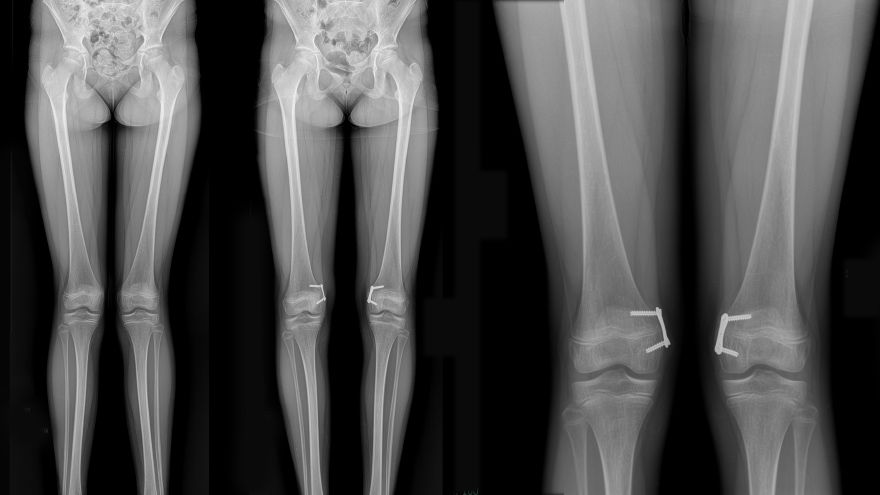

Images left to right: Patient presenting with genu valgum, post-genu valgum with posts in place, and detail of post positioning.